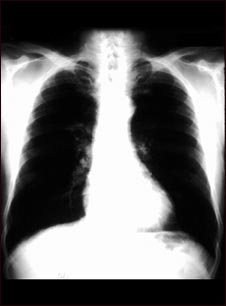

Cáncer bronquial - radiografía de tórax

Ésta es una radiografía de tórax de una persona con cáncer bronquial. En esta vista frontal, los pulmones aparecen como dos áreas oscuras y el corazón y otras estructuras como las áreas claras visibles en la mitad del tórax. Las áreas claras que aparecen como ramificaciones sutiles extendiéndose desde el centro hacia los pulmones son cancerosas.